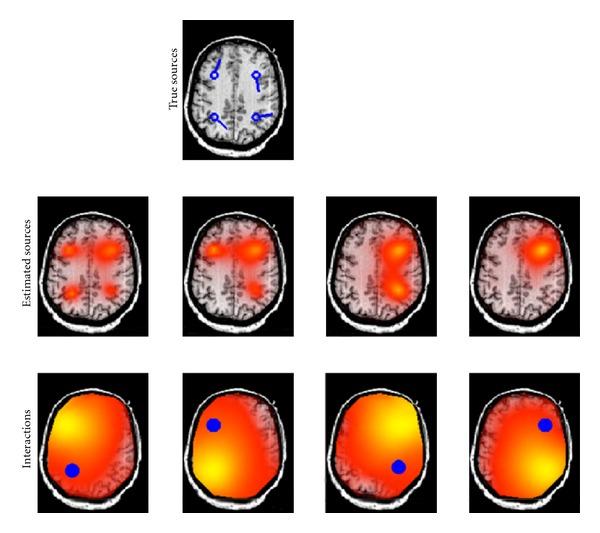

To address the problem of mixing in EEG or MEG connectivity analysis we exploit that noninteracting brain sources do not contribute systematically to the imaginary part of the cross-spectrum. Firstly, we propose to apply the existing subspace method "RAP-MUSIC" to the subspace found from the dominant singular vectors of the imaginary part of the cross-spectrum rather than to the conventionally used covariance matrix. Secondly, to estimate the specific sources interacting with each other, we use a modified LCMV-beamformer approach in which the source direction for each voxel was determined by maximizing the imaginary coherence with respect to a given reference. These two methods are applicable in this form only if the number of interacting sources is even, because odd-dimensional subspaces collapse to even-dimensional ones. Simulations show that (a) RAP-MUSIC based on the imaginary part of the cross-spectrum accurately finds the correct source locations, that (b) conventional RAP-MUSIC fails to do so since it is highly influenced by noninteracting sources, and that (c) the second method correctly identifies those sources which are interacting with the reference. The methods are also applied to real data for a motor paradigm, resulting in the localization of four interacting sources presumably in sensory-motor areas.

为了解决 EEG 或 MEG 连接分析中的混叠问题,我们利用非交互脑源不会系统地对互谱的虚部做出贡献这一特性。首先,我们建议将现有的子空间方法“RAP-MUSIC”应用于从互谱虚部的主导奇异向量中找到的子空间,而不是应用于传统上使用的协方差矩阵。其次,为了估计与每个相互作用的源,我们使用了一种改进的 LCMV-波束形成方法,其中每个体素的源方向是通过相对于给定参考最大化虚相干性来确定的。只有在相互作用的源数量为偶数的情况下,这两种方法才能以这种形式应用,因为奇数维子空间会塌缩到偶数维子空间。模拟表明:(a)基于互谱虚部的 RAP-MUSIC 准确地找到了正确的源位置;(b)传统的 RAP-MUSIC 无法做到这一点,因为它受到非相互作用源的高度影响;(c)第二种方法正确地识别了与参考相互作用的那些源。这些方法也应用于运动范式的真实数据,导致四个相互作用的源在感觉运动区域的定位。